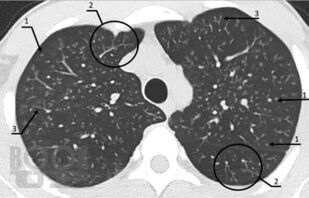

Сборник включает вызвавшие наибольший интерес аудитории лекции и доклады на различных научно-практических конференциях в 2020-2021 гг. по актуальным проблемам пульмонологии и аллергологии детского возраста, таким как: современные методы диагностики и лечения, острые и хронические инфекционно-воспалительные и аллергические заболевания органов дыхания, муковисцидоз, туберкулез органов дыхания, COVID-19, а также различные другие информационные материалы. Ежегодник адресован практикующим детским пульмонологам и аллергологам.